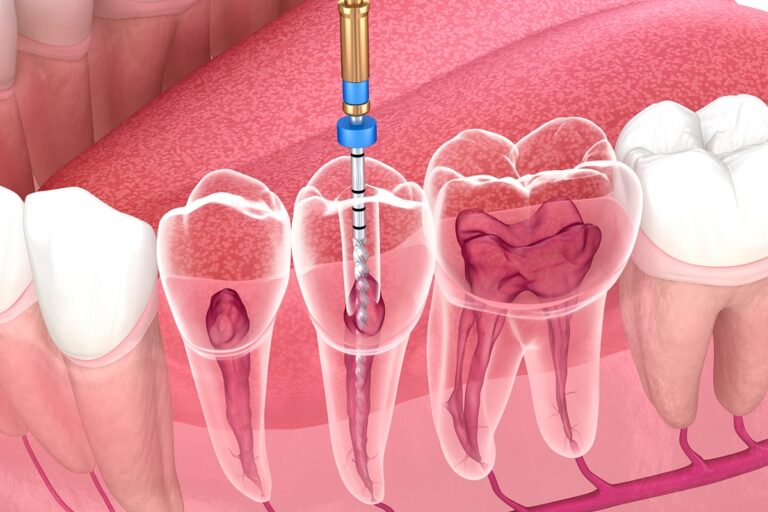

درمان ریشه تخصصی

◦ درمان ریشه برای دندان هایی با انحنا شدید ◦ دندان هایی با کانالهای بسته ◦ درمان مجدد دندانهای شکست خورده ◦ درمان ریشه دندانهای عقل قابل نگهداری ◦ درمان دندانهای نرمال